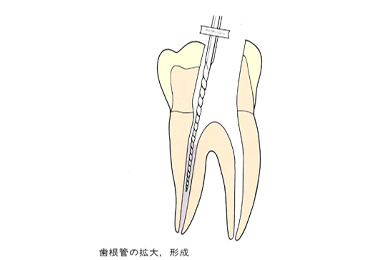

1

抜髄(バツズイ)

虫歯が進行していくと冷たいものがしみます。そのままにしておくと冷たいものだけでなく、熱いコーヒーなどでも痛みがでてきます。これが歯髄炎(シズイエン)です。

神経まで炎症が波及して、自然に治ることはありません。歯医者ではそのような場合に「神経を取る」治療を行います。この「神経を取る」治療のことを抜髄(バツズイ)と言うのです。

下の写真を見てください。この神経取れると思いますか。

本物の歯の神経の管を染めて、その走行を調べた写真です。複雑怪奇です。実際、この神経を全部きれいにとり切るのは不可能です。

患者さんは、神経を取るというと一本の糸をすーと引くと取れてくるようなイメージをお持ちのようです。私も歯科医になる前はそんなイメージを持っていましたが、神経を取る処置はまるで難攻不落の敵に立ち向かうほどの忍耐力を必要とします。大臼歯などは2時間ぐらいかかることもあります。

虫歯菌に侵された神経(歯髄)や汚染された象牙質をリーマー、Kファイル、Hファイルなどを使用して取り除いていきます。

ファイルやリーマーを使用して神経を取ります。

神経を取ったらそれで治療が終了ではありません。

その後神経があった管の中にばい菌が侵入しないように薬を詰めていきます。普通はガッタパーチャポイントと呼ばれる材料とシーラーという薬剤を併用して根管(コンカン)を封鎖します。

水色の部分がガッタパーチャポイントとシーラーです。

ガッタパーチャポイントです。この薬とシーラーを根の中に入れていきます。

抜髄は先生とあなたとの根気くらべです。患者さんもお口を開け続けるのは大変ですが、先生も大変です。 神経の走行は複雑怪奇です。根管の数も入り口も同じ歯は一つとしてありません。この神経を取る抜髄治療は、「難敵に立ち向かう意気と根気」を必要とします。